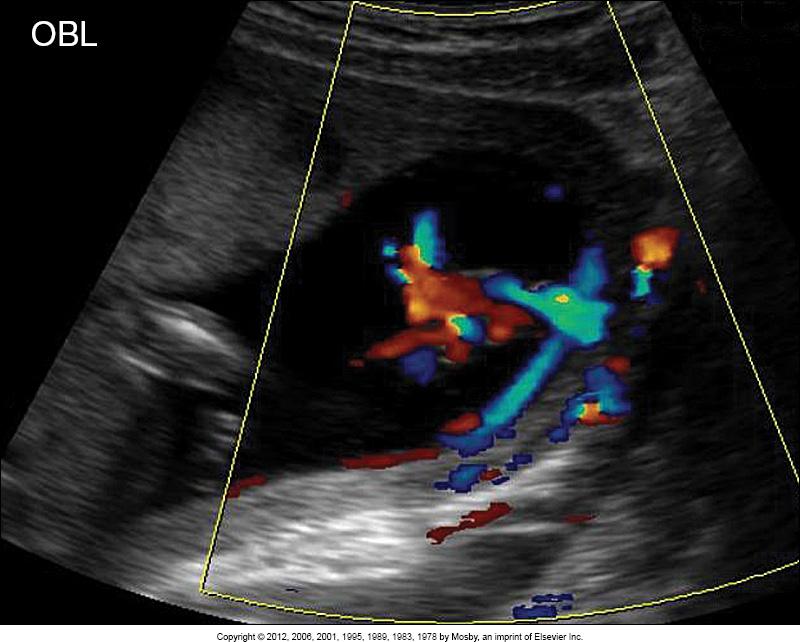

what does this image show?

battledore placenta